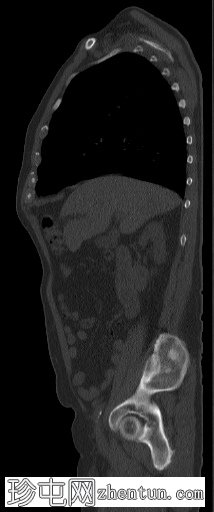

8.png

矢状位

脊柱、肋骨、骨盆、颅骨、肩胛骨、胸骨、左侧肱骨和双侧股骨干可见多处放射性示踪剂摄取异常增高,与SPECT-CT扫描图像上显示的硬化病灶相对应。双肾未见放射性示踪剂活性。

骨骼内多处局灶性放射性示踪剂摄取增高,符合骨转移;肾脏内无放射性示踪剂活性,与超扫描结果一致。